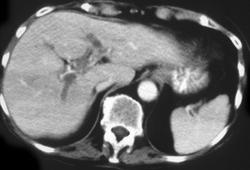

Hepatoma